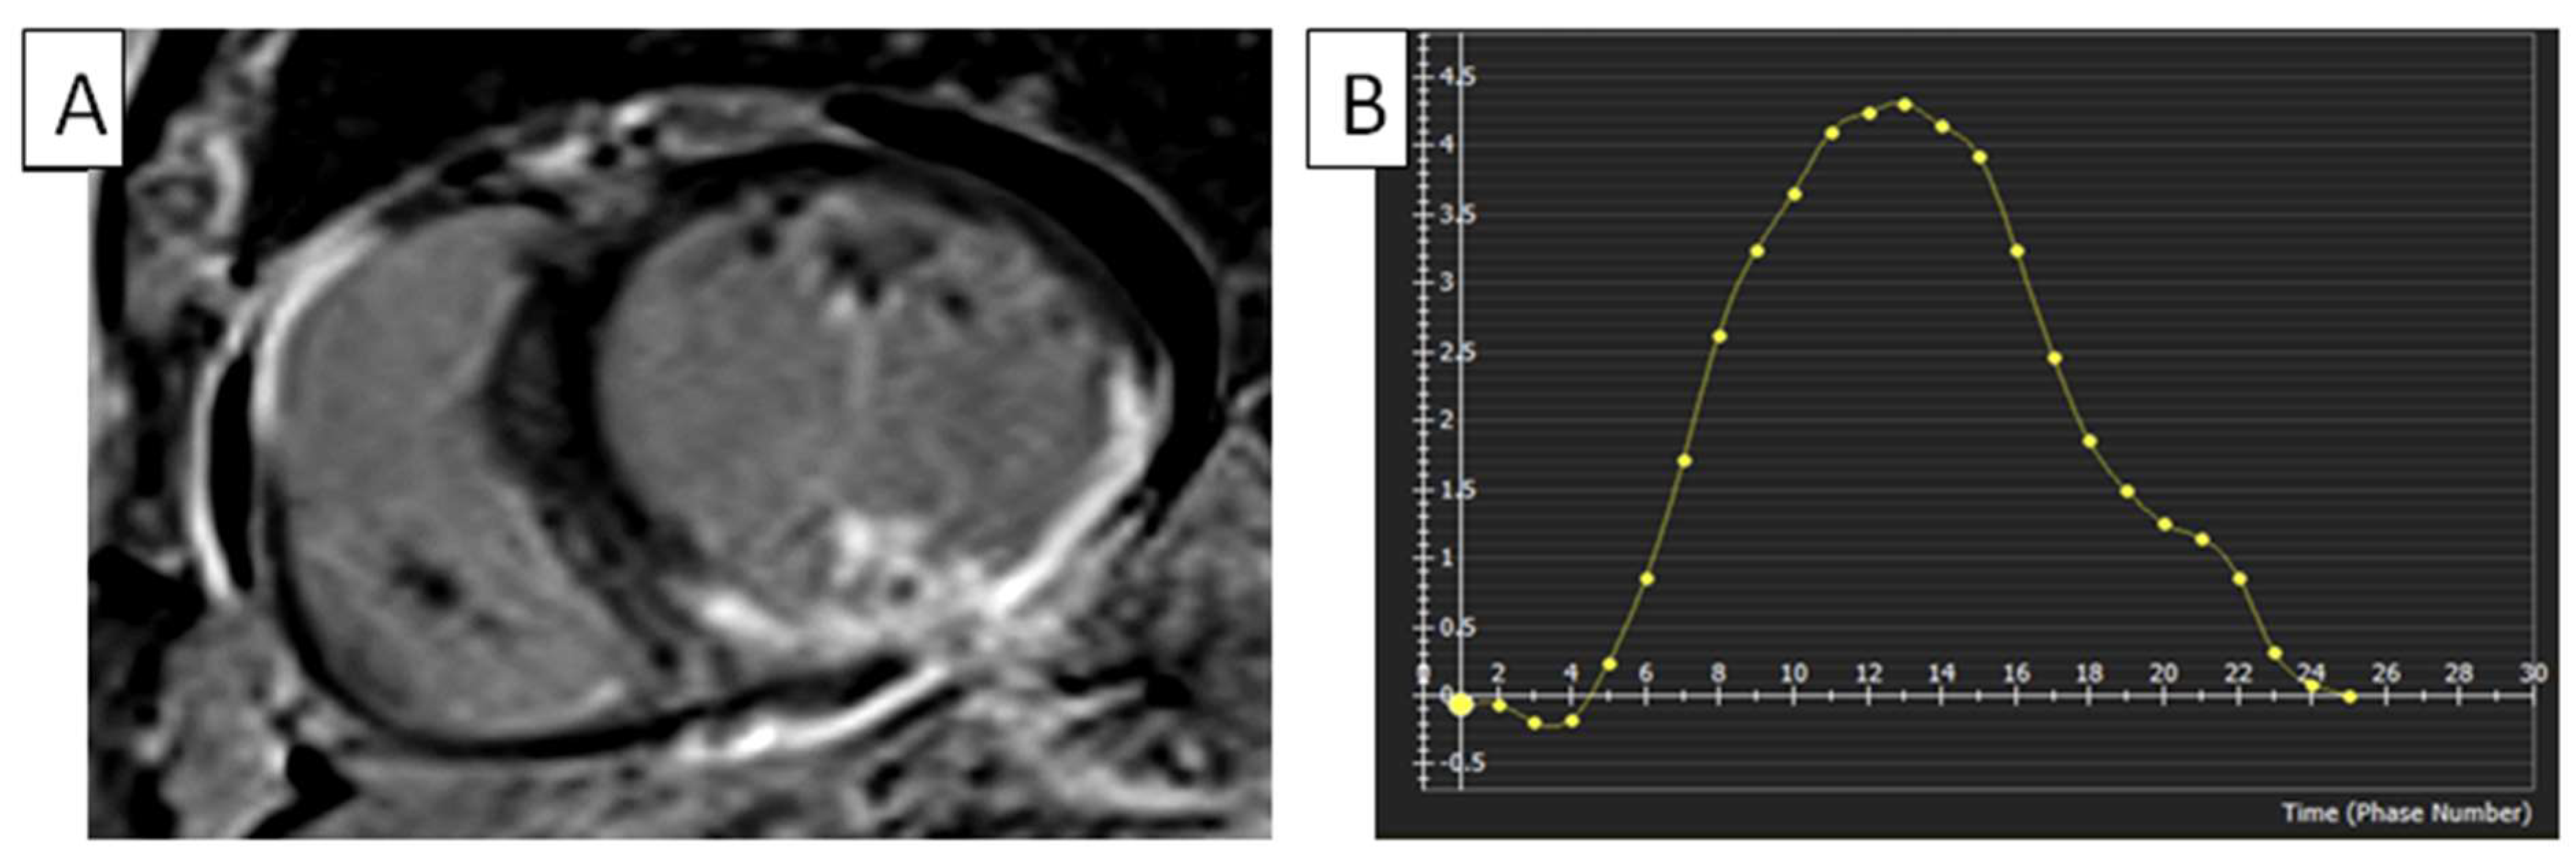

Figure 5.

RV infarction. (A) Short-axis phase-sensitive inversion recovery, late-phase contrast enhancement cMRI view of a patient with inferolateral LV and RV lateral wall infarction. (B) Two-dimensional myocardial FTI on a short-axis cine SSFP image shows an impaired RV radial strain. Radial strain values are also usually in the positive range. On the graph, the vertical axis shows the radial strain and the horizontal axis shows the time in milliseconds. FTI, feature tracking imaging; LV, left ventricle; RV, right ventricle; cMRI, cardiac magnetic resonance imaging; SSFP, steady-state free precession.